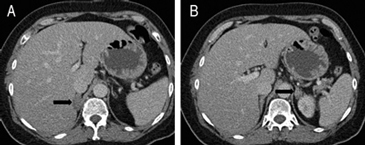

En la TC no contrastada las glándulas suprarrenales normales son homogéneas y simétricas, con una densidad muy similar a la del parénquima renal adyacente (Figura 1 a). Con un medio de contraste ev la glándula suprarrenal se opacifica en forma homogénea, similar al hígado o al bazo (Figura 1 b). Si la cantidad de tejido adiposo retroperitoneal es abundante las glándulas suprarrenales pueden aparecer enteramente rodeadas por grasa y su delimitación es más fácil (Figura 2 a); lo inverso ocurre en pacientes muy delgados con escasa grasa retroperitoneal (Figura 2 b). En RM, en secuencias ponderadas en T1 y T2 convencionales tienen una intensidad de señal homogénea, hipointensa respecto de la grasa adyacente e iso o hipointensa con respecto del parénquima hepático (Figura 3 a y b). En los cortes coronales se aprecia mejor la forma y la posición de las glándulas suprarrenales (Figura 3 c).

Figura 3. Glándula suprarrenal normal en resonancia magnética. (a) Cortes axial ponderado en T1 la señal de la glándula normal (flecha negra) es hipointensa respecto a la grasa retroperitoneal e isointensa respecto al parénquima hepático. (b) Cortes axial ponderado en T2 en que se muestra la glándula suprarrenal derecha (flecha blanca) y (c) corte coronal ponderado en T2 en que se muestra la glándula suprarrenal derecha (flecha blanca) y la glándula suprarrenal izquierda (flecha negra) con similares características de intendidad de señal. 3. Causas y prevalencia de las lesiones suprarrenales